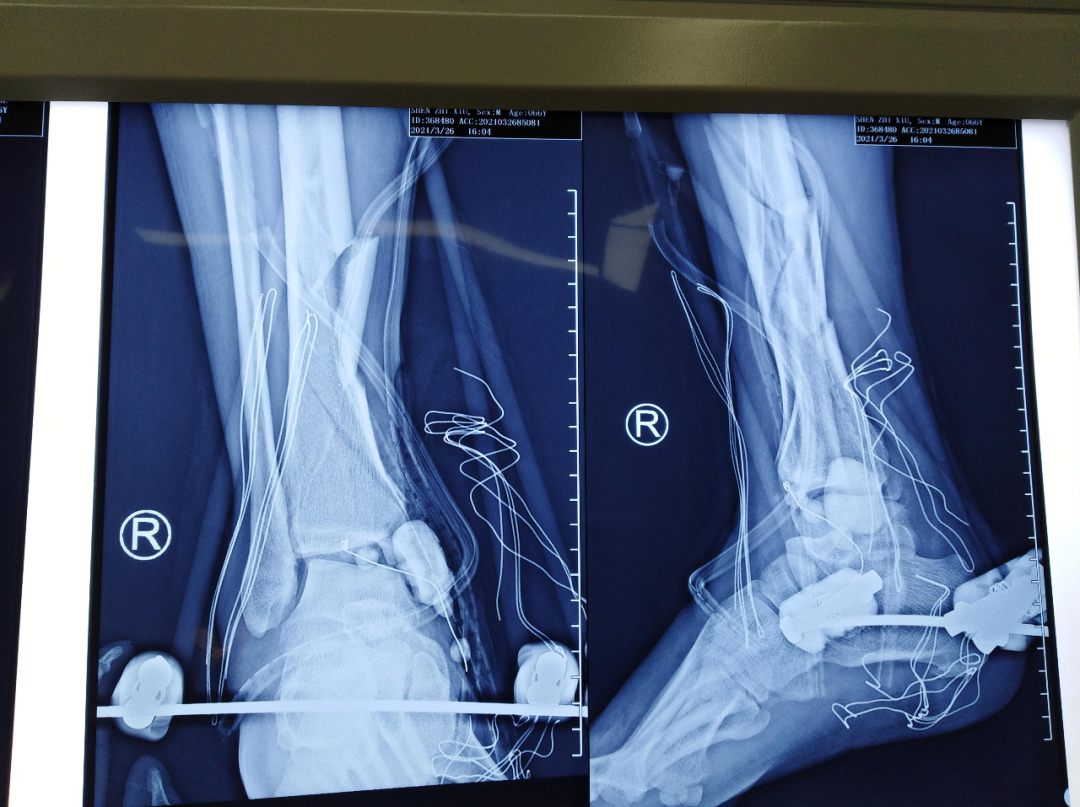

术前平片

该患者车祸伤入院,入院查体可见右内踝皮肤缺损面积约5cm*10cm,右足背部皮肤脱套伤,内踝缺如。患者既往高血压、糖尿病,一直服用利血平及阿司匹林。利血平一般建议停用2周,阿司匹林建议停用1周方能进行麻醉。不手术,患者开放性损伤,持续流血状态,失血过多会发生生命危险。手术的话,服用利血平有术中发生血压不能维持,呼吸心跳骤停的风险。麻醉医师团队及创伤骨科医师团队面临双重风险,两害相权取其轻。患者开放性损伤,时间就是生命。面对困难,勇于承担,经患者及家属同意,第一时间进行了第一次清创+外固定支架固定+VSD负压引流手术。后续又进行了第二次清创+外固定支架调整+抗生素骨水泥链植入+克氏针固定踝关节骨折+VSD负压引流手术。第三次清创+骨折复位螺钉内固定+内踝重建+Ilizarov环形外固定固定+VSD负压引流手术。手术均进行顺利。

第一次手术拍片